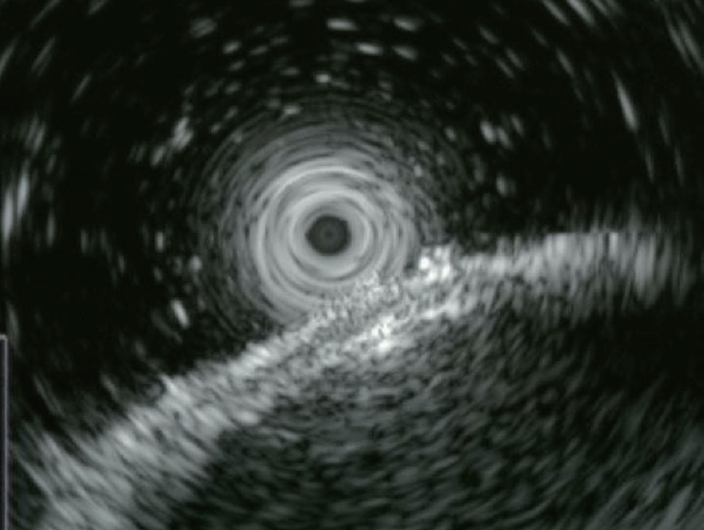

내시경 초음파(endoscopic ultrasound, EUS)에서 병변은 serosa layer에 국한된 균일한 저에코성(hypoechoic) 병변으로 관찰되었으며 muscularis propria와는 명확히 구분되어 있어 위장관벽 기원보다는 외부 기원의 가능성을 고려하게 하였다(Fig. 3). 그러나 종괴의 실제 기원층이 확정되지 않아 조직학적 판단 또는 영상학적 추가 평가가 필요하다고 판단되었다.

Figure 3.

Endoscopic ultrasonography. A homogeneous hypoechoic mass confined to the serosal layer without clear layer of origin.